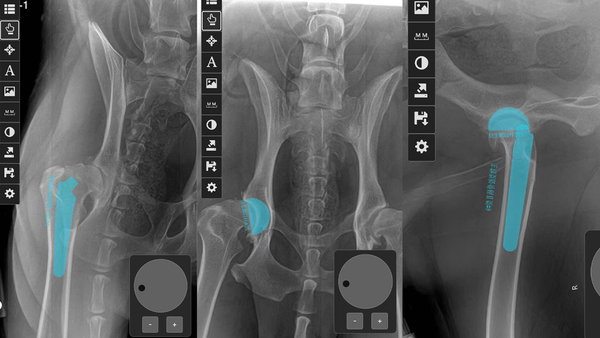

🩺Đánh giá và lập kế hoạch trước phẫu thuật thoái hóa khớp háng ở chó – Lên kịch bản từng milimet

🔹 Trước phẫu thuật, các bác sĩ đã sử dụng phần mềm chuyên dụng iBlueVet để mô phỏng cấu trúc khớp háng của bệnh nhân.

🔹 iBlueVet giúp:

- Phân tích kích thước, góc xoay, độ nghiêng xương.

- Lựa chọn kích cỡ implant chính xác.

- Lập kế hoạch mổ tối ưu để giảm rủi ro lệch trục, trật khớp.